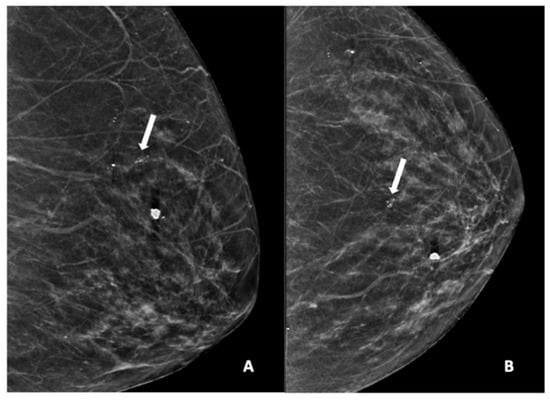

Figure 2, Figure 3, Figure 4, Figure 5 and Figure 6 show examples of the different microcalcification morphologies and distributions, while Figure 6 shows an example of a mammographic mass and an image of a complementary ultrasound assessment of the mass.

Figure 3.

Mammogram study of a left breast in (A) MLO view and (B) CC view, showing a group of pleomorphic calcifications in the upper mid-quadrant (arrow), reported as BI-RADS 4 lesion. These calcifications were HPE-proven DCIS. There were also benign coarse calcifications in the upper inner quadrant.